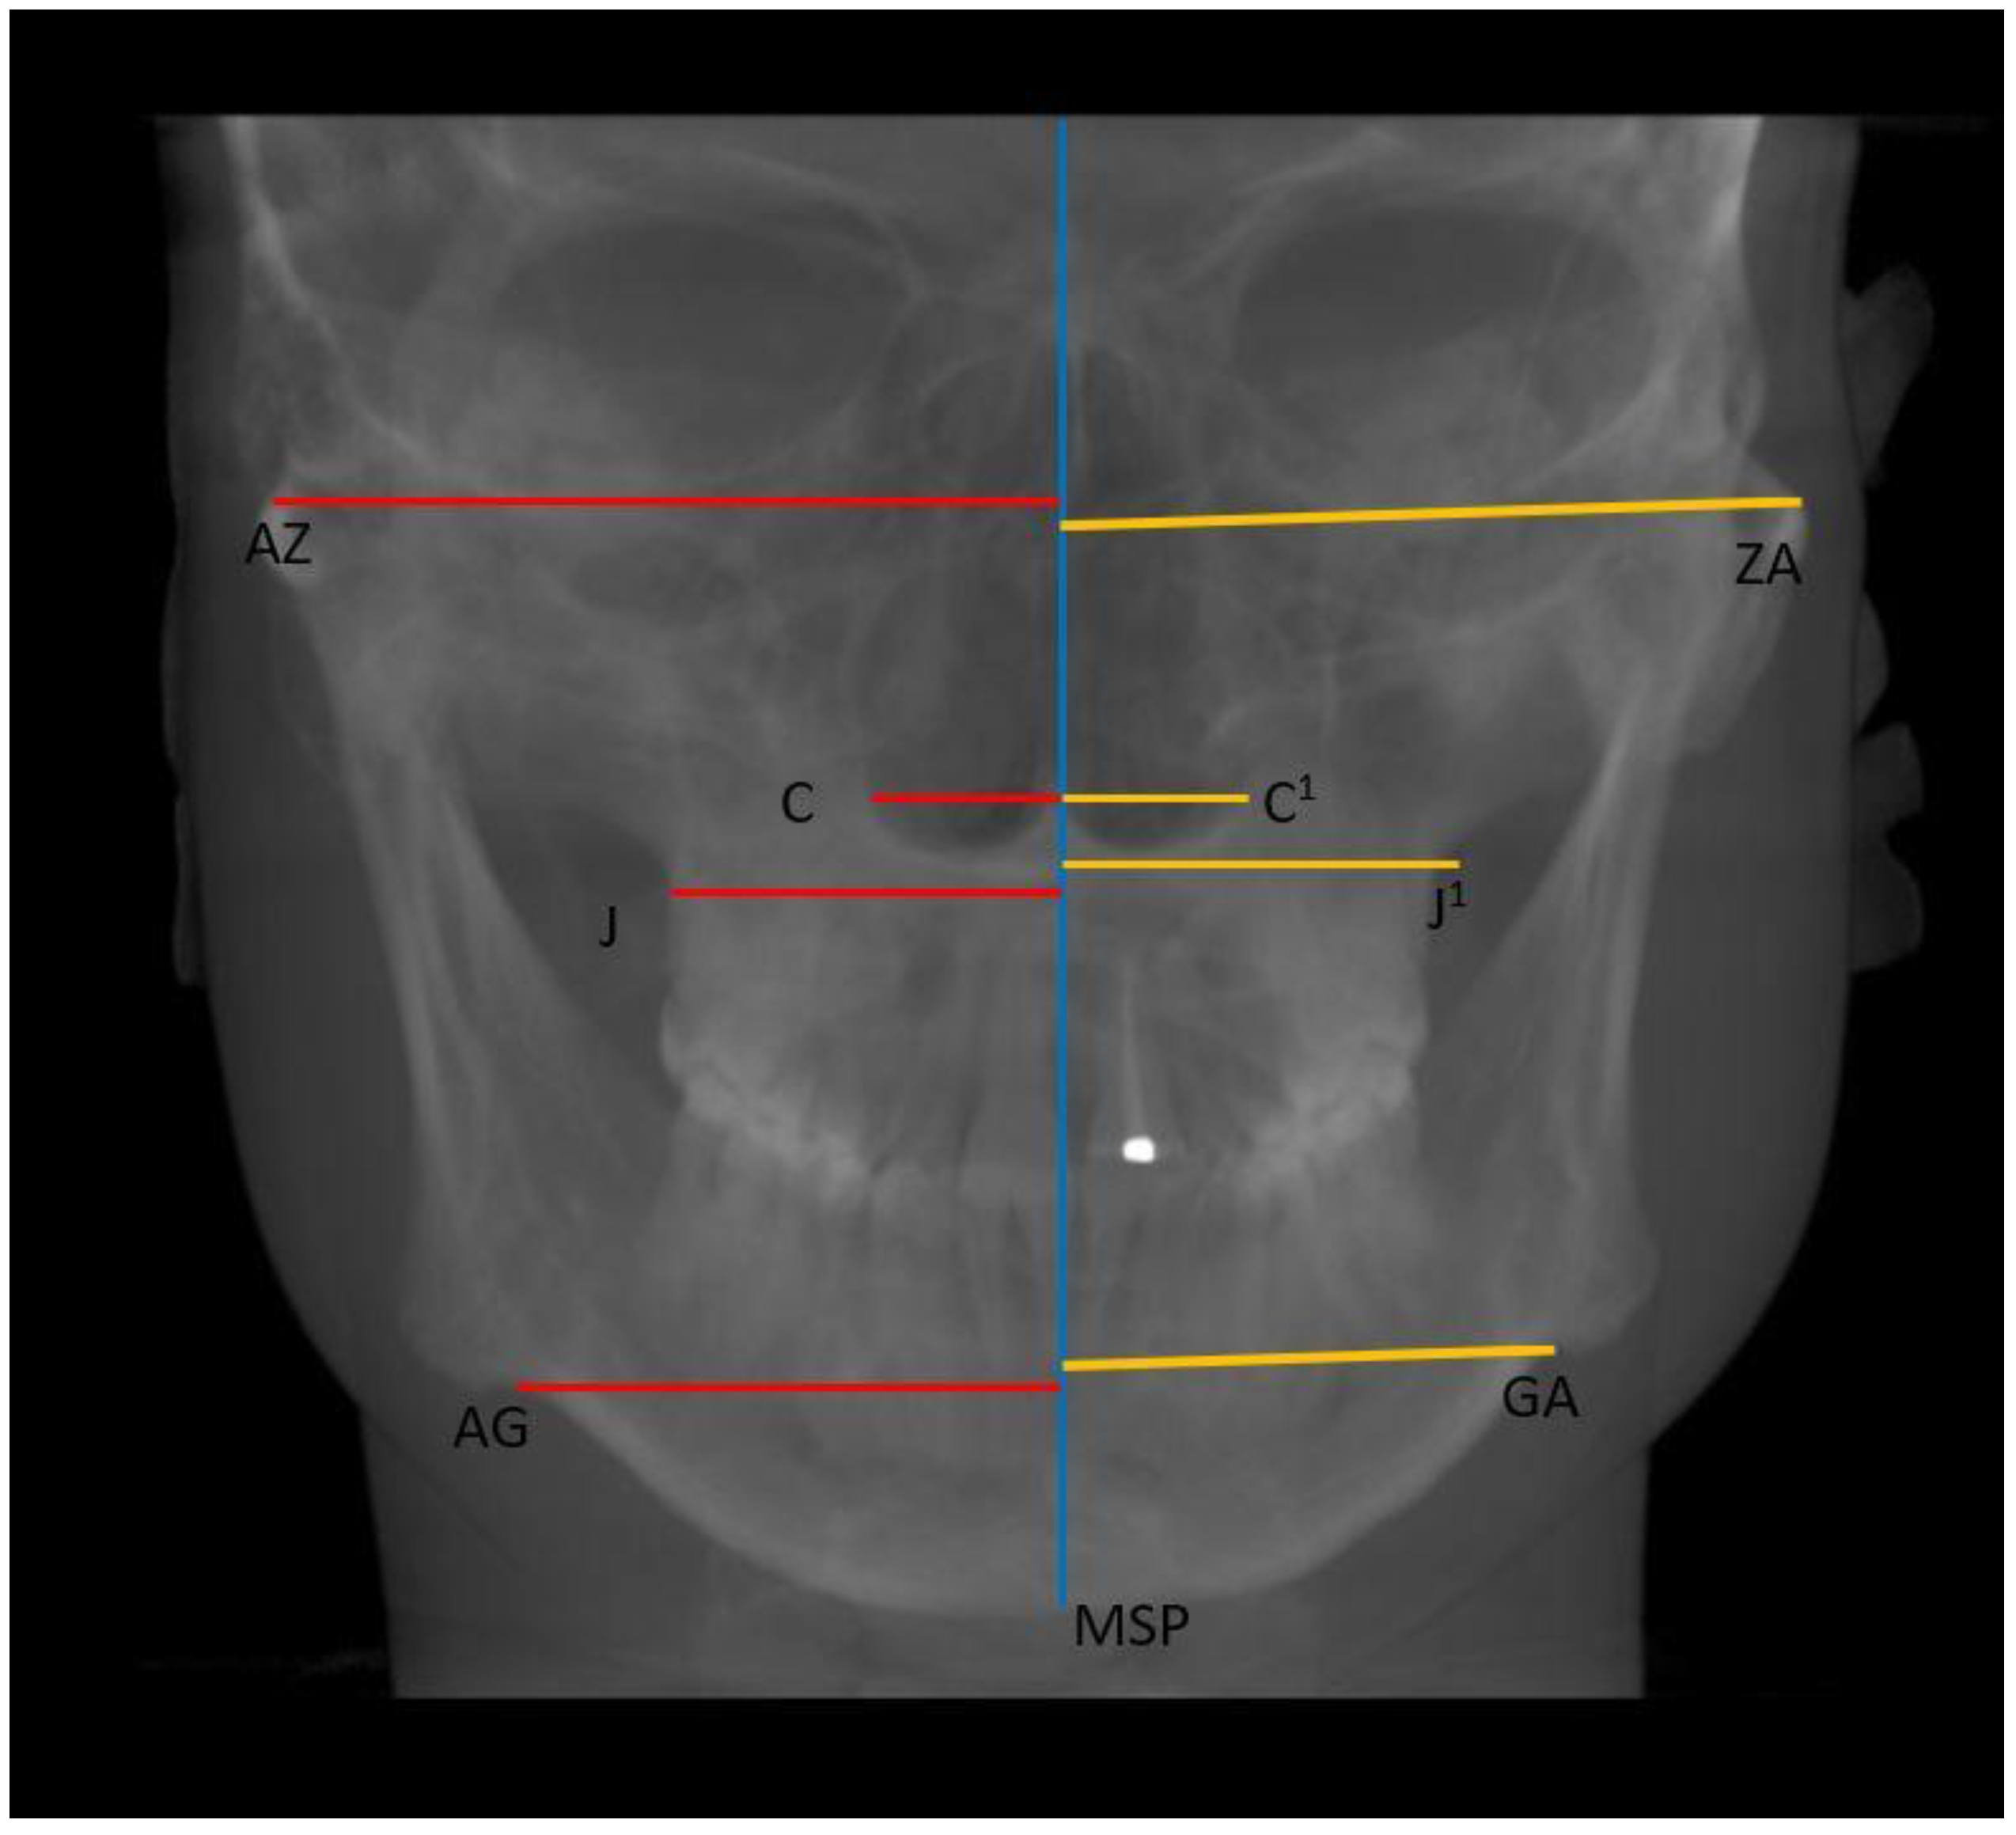

- Horizontal: Nasal cavity width (C–C1), distance between zygomaticofrontal sutures (ZR–ZL), distance between the centres of the roof of the zygomatic arch (AZ–ZA), distance between the jugal processes (J–J1), and distance between the antegonial points (AG–GA) (Figure 4);